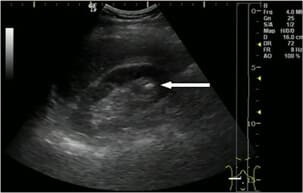

Вторият случай е свързан с киста с диаметър 3 cm. Болестта обикновено преминава без симптоми. Не боли, резултатите са добри, уринирането протича гладко. Ето защо кистата беше толкова голяма. 22-годишното момиче се страхуваше от операция. Изписахме й Nefro Aktiv . В рамките на месец повторният преглед не показа никаква патология.